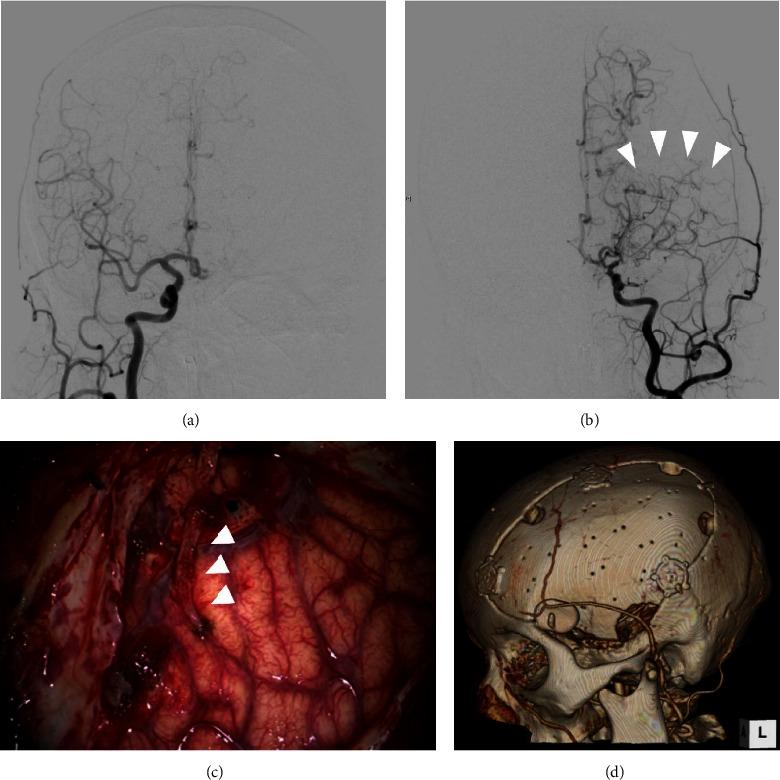

Moyamoya disease is often diagnosed after intracranial hemorrhage in adult patients. Here, we report a case of unilateral moyamoya disease treated with indirect revascularization combined with cranioplasty after treatment for acute subdural hematoma and subcortical hemorrhage. A middle-aged woman with disturbed consciousness was transferred to our hospital. Computed tomography (CT) revealed an acute subdural hematoma with left temporoparietal subcortical hemorrhage. Three-dimensional CT angiography indicated a scarcely enhanced left middle cerebral artery (MCA) that was suspected to be delayed or nonfilling due to increased intracranial pressure. Subsequently, hematoma evacuation and external decompression were performed. Postoperative digital subtraction angiography (DSA) revealed stenosis of the left MCA and moyamoya vessels, indicating unilateral moyamoya disease. Forty-five days after the initial procedure, we performed encephalo-arterio-synangiosis (EAS) using the superficial temporal artery simultaneously with cranioplasty for the skull defect. The modified Rankin Scale score of the patient one year after discharge was 1, and the repeat DSA showed good patency of the EAS. Revascularization using EAS in the second step can be an option for revascularization for hemorrhagic moyamoya disease if the patient required cranioplasty for postoperative skull defect after decompressive craniotomy.

摘要

烟雾病在成年患者中常于颅内出血后被诊断出来。在此,我们报告一例单侧烟雾病患者,在接受急性硬膜下血肿和皮质下出血治疗后,采用间接血管重建术联合颅骨成形术进行治疗。一名意识障碍的中年女性被转诊至我院。计算机断层扫描(CT)显示急性硬膜下血肿伴左侧颞顶叶皮质下出血。三维CT血管造影显示左侧大脑中动脉(MCA)强化极少,怀疑因颅内压升高导致延迟或未显影。随后,进行了血肿清除和外减压术。术后数字减影血管造影(DSA)显示左侧MCA狭窄及烟雾血管,提示单侧烟雾病。初次手术后45天,我们在颅骨缺损修补术的同时,使用颞浅动脉进行了脑动脉吻合术(EAS)。患者出院一年后的改良Rankin量表评分为1分,复查DSA显示EAS通畅良好。如果患者在减压性开颅术后因颅骨缺损需要进行颅骨成形术,第二步采用EAS进行血管重建可作为出血性烟雾病血管重建的一种选择。